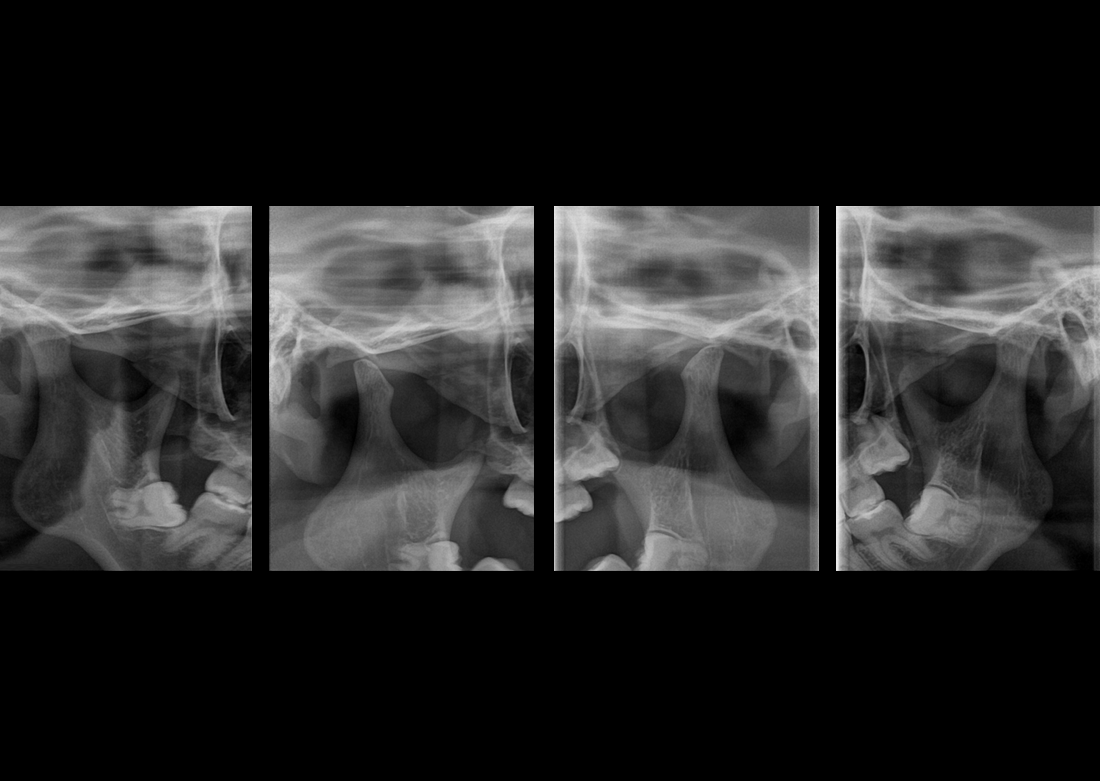

Cephalometric

MÜKEMMEL GÖRÜNTÜ KALİTESİ

KLİNİK FOTOĞRAFLAR

Yılların tecrübesi ve geliştirdiği know-how teknolojileri ile muhteşem teşhis görüntüleri yaratmak Genoray firmasının herzaman gururu olmuştur..